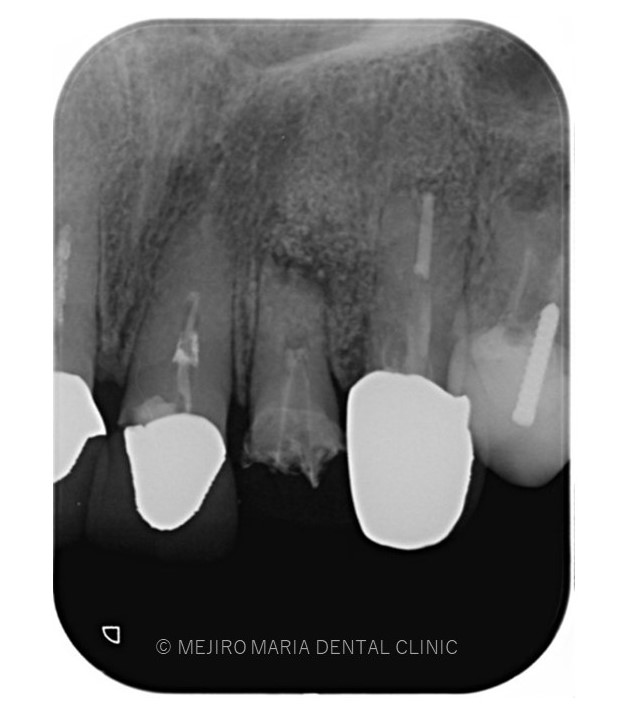

でのリカバリー_治療前感染した人工骨が確認できるレントゲン画像.jpg)

でのリカバリー_治療前、感染した人工骨部分レントゲン画像.jpg)

今回の症例は、他院にて歯根端切除術を行った根尖部(歯の根の先)に充填された人工骨の感染が原因と考えられます。

しかし、歯根端切除術の成功率は100%ではなく、多くの症例の中には少なからず再度オペを行うケースも出てくる可能性があります。

万が一、歯根端切除術が失敗した場合、人工骨の感染はより事態を悪化させることになります。

歯根端切除術後は術後の透過像で治癒を確認することが重要であり、感染が除去できていれば骨は患者自身の力で自然に再生を行うことになるので、人工骨を充填することはリスクが高い行為であると考えます。